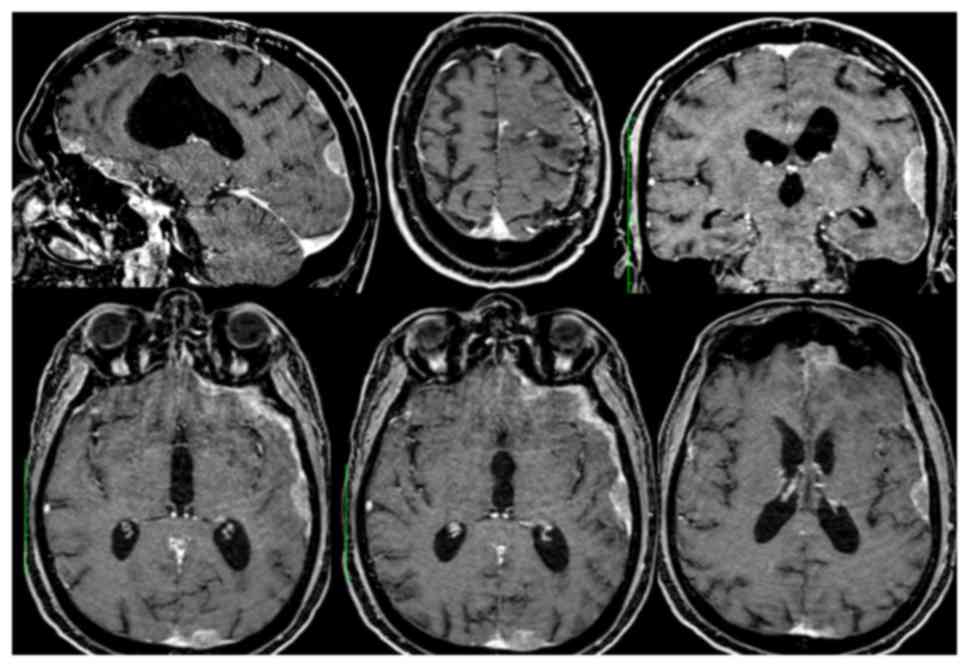

In August, on the 6th postoperative month, a control brain MRI documented slight volumetric reduction of the two left frontal centronecrotic nodules (10 mm vs. 13 and 5 mm vs. 10 mm) and of the lesion of the corpus callosum (7 mm vs. 20 mm) (intracerebral partial response). However it also showed contrast-enhancing leptomeningeal thickening in the left temporal lobe (maximum 14 mm), left ethmoido-sphenoidal emiplanum (maximum 12 mm) and left portion of the tentorium (maximum 10 mm) (Fig. 3). Moreover, a subcutaneous nodule was clinically evident in the left frontal region, at the level of the previous craniotomy. Despite the new findings the patient was still clinically stable.

Figure 3.

Contrast-enhanced brain magnetic resonance imaging at postoperative month 6, following adjuvant temozolomide. A paracentimetric frontal centronecrotic nodule with peripheral enhancement is evident anteriorly to the previous surgical bed. Left fronto-temporal and fronto-basal diffuse leptomeningeal neoplastic ‘en plaque’ seeding are also present.